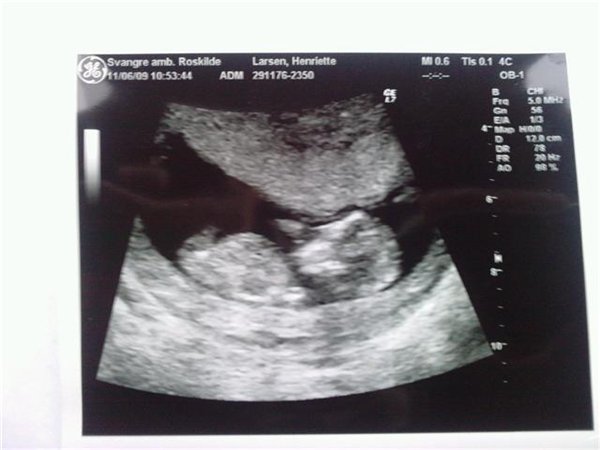

talle var 435 udfra en aldre på 32 år små ryger,højte 163 vægt før gravid 50,5 nu 60,4 kunne hun oplyse.

Men med min scanningen også var= 2340.

Nakkefolden var 1,2 mm.

Ret flot lille sagde hun.